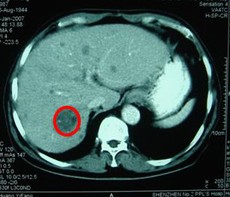

男,63歲,原發(fā)性肝癌晚期。AFP入院時(shí)為13000ng/L, 右肝區(qū)巨大腫瘤約為13×10=130 cm2。治療方案:介入栓塞一個(gè)月后肝動(dòng)脈插管皮下置泵灌注今又生和5-FU。治療后:腹脹,腹痛消失,食欲增加,體重有所增加。AFP介入栓塞后為6000ng/L,灌注今又生和5-FU后為4ng/L,右肝腫瘤縮小至3×2cm。

治療前

治療后